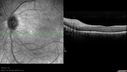

SPECTRALIS-SD-OCT SCAN: The OCT scan shows macular edema in both eyes with a serous macular detachment in the left eye. There are intraretinal cysts and retinal atrophy in the far periphery. The OCT scan does show atrophy of the outer retina.